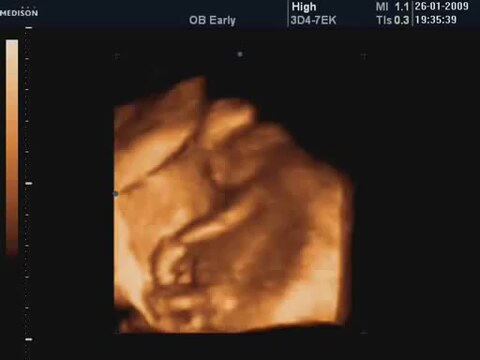

15 Haftalik Bebeğin 4 Boyutlu Ultrason Görüntüsü